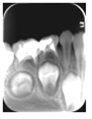

65MO深大龋洞,色棕黄,质软,叩痛(+),不松动,牙龈红肿,未见瘘管。 X线片示:冠部低密度影达髓腔,根分歧区大面积低密度影,近远中根内侧壁见吸收。25牙胚存,未拍全。 64MO深大龋洞,色棕黄,质软,叩痛(+),不松动,牙龈略红肿。 X线片示:根分歧区密度减低。 84OD深大龋洞,色棕黄,质软,叩痛(-),不松动, 85MO牙色充填体周围见龋坏,色黑,质软,叩痛(±),不松动,龈无异常。 X线片示:根周见低密度影,44,45牙胚存,未拍全。 54DOL深大龋洞,色黑,质软,叩痛(-),不松动, 55O窝沟色黑,卡探针,叩痛(-),不松动,龈无异常。 74OD,75MO半年前曾于外院行充填治疗,现检查见充填体边缘色黑,卡探针,充填体略有松动。

诊断:64,65,84,85慢性根尖周炎;54DOL深龋,55O中龋;74OD,75MO继发深龋 处置:64,65,84,85根管治疗 54DOL,55O行充填治疗 74OD,75MO去除旧充填体后充填治疗

乳牙根管治疗术是治疗乳牙根尖周病的有效方法,通过根管预备和药物毒去除感染物质对根尖周组织的不良刺激,并用可吸收的充填材料充填根管,促进根尖周病愈合。 在第一恒磨牙未完全萌出之前,为防止乳牙早失造成第一恒磨牙近中移位,对于第二乳磨牙的较大面积根尖周病变我们采取保守治疗,根管治疗后需定期复查,一旦发生病变扩大及时拔除,在此病例中第一恒磨牙未完全萌出,我们对65,85进行试保留,半年后临床检查无异常,x线片显示病变较初诊时缩小,建议继续观察。